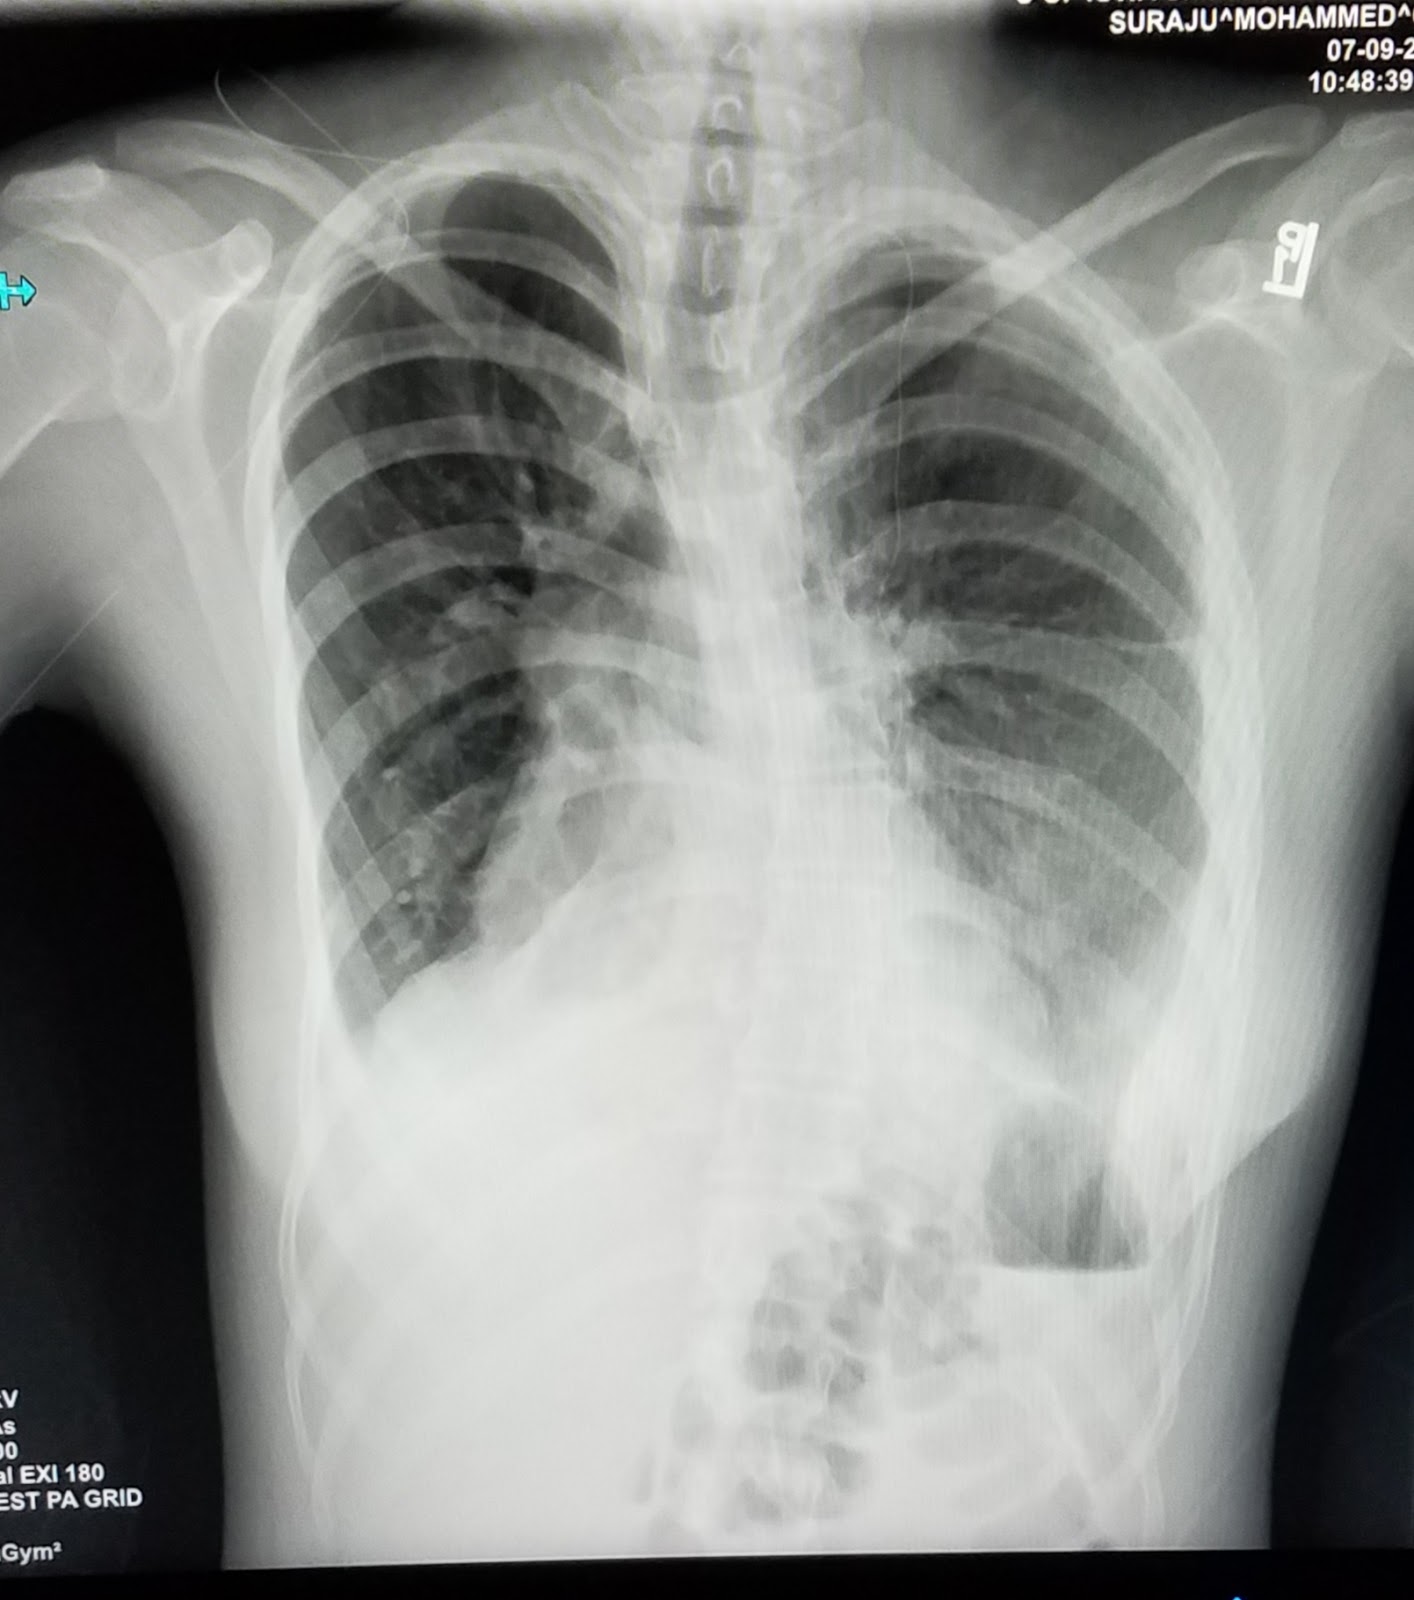

She also got an x ray today. They wanted to see her diaphragm and lungs. She was so patient. The technician remembered us and we had a good little laugh about old times. We are seeing many nurses and staff that were here ten plus years ago.

Here is her new diaphragm. Things look good. It's reassuring to know that organs are in their proper places! Her left side lung is more visible now.